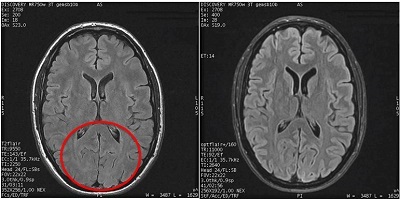

Use T2 FLAIR to acquired images to suppress bright CSF signal that is adjacent to fluid filled structures.

Figure 3. T2 FLAIR brain